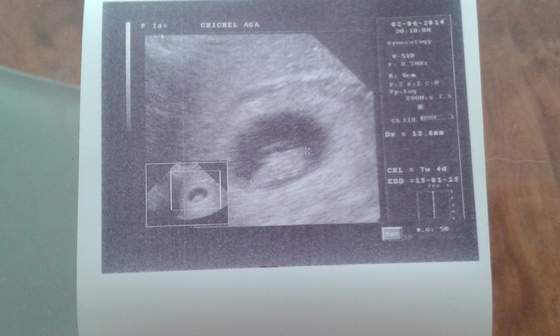

super wiadomosc na poczatek tygodnia !!!!Zobacz załącznik 627187kochane jest ok krwiak sie wchłonoł serducho bije dzidzia duża 13,6mm